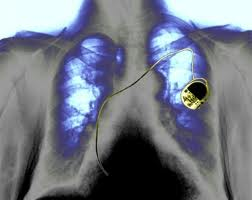

Η ανθρώπινη καρδιά αποτελείται από εκατομμύρια κύτταρα, ωστόσο, σύμφωνα με τους ειδικούς, λιγότερα από 10.000 είναι τα υπεύθυνα για τον έλεγχο του καρδιακού παλμού. Η γήρανση του οργανισμού καθώς και οι ασθένειες μπορούν να οδηγήσουν σε καρδιακές αρρυθμίες – ακόμη και σε «πάγωμα» του καρδιακού παλμού, που ονομάζεται ανακοπή καρδιάς. Σε τέτοιες περιπτώσεις οι γιατροί εμφυτεύουν έναν βηματοδότη στην καρδιά ο οποίος λειτουργεί με μπαταρία και ρυθμίζει τον καρδιακό παλμό.